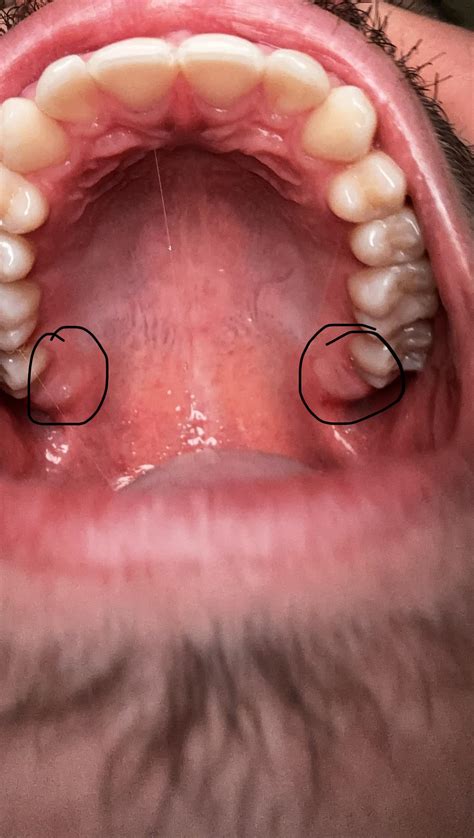

The journey of wisdom teeth growing in is rarely symptom-free. Because your jaw may be too small to accommodate these extra molars, they often become “impacted,” meaning they are trapped beneath the gum line or against existing teeth. Recognizing these symptoms early can help you seek professional dental care before the situation escalates into a severe infection.

• Swelling and Tenderness: The gum tissue around the area often becomes red, puffy, and sore to the touch.